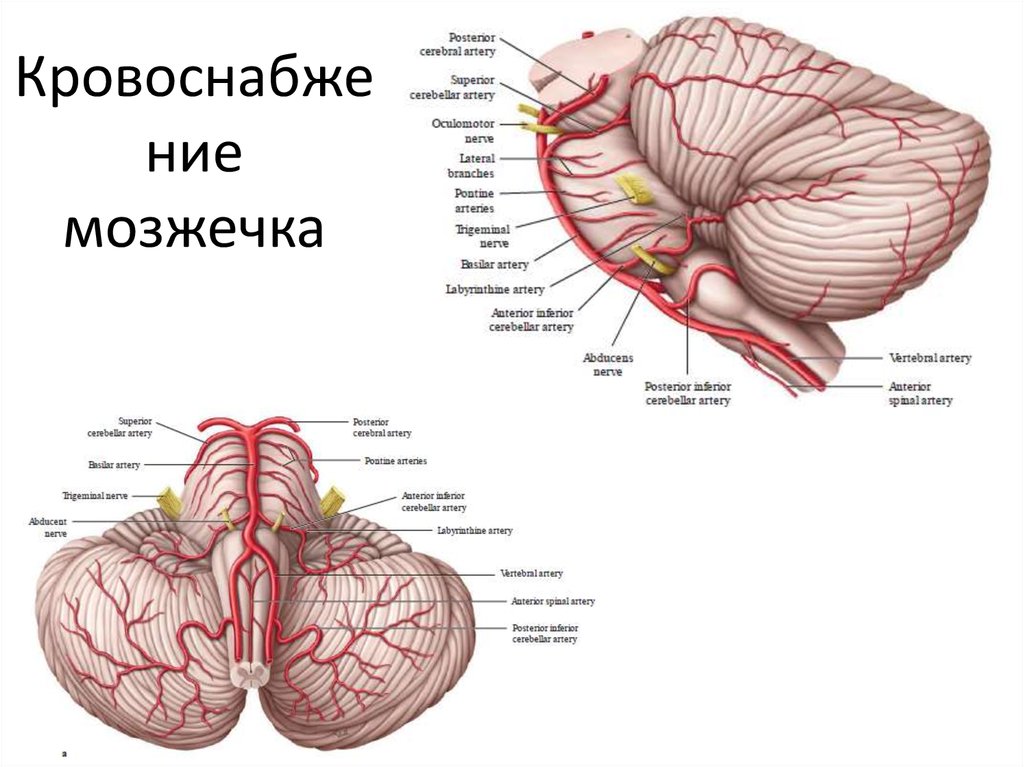

Анатомия: Задняя соединительная артерия мозга